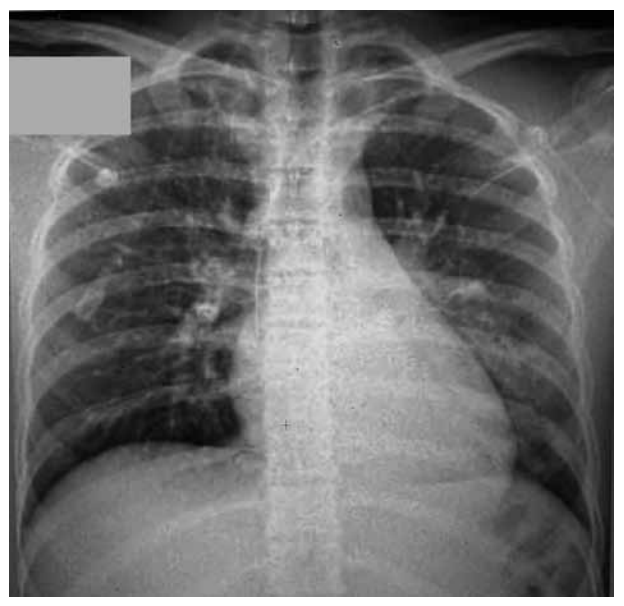

Uma criança de 11 anos deu entrada no pronto-socorro com cefaleia e dor torácica associadas à temperatura de 38,5 ºC.

Clinicamente, apresentava uma ausculta com diminuição do murmúrio vesicular na base esquerda, tempo de enchimento

capilar de 4 segundos e pressão arterial de 90 x 55. Foi puncionado acesso venoso, foram iniciadas expansões volêmicas

de 20 mL/kg por duas vezes no pronto-socorro, e a criança foi encaminhada para a UTI. Foram solicitados exames laboratoriais e raio-X de tórax (figura a seguir). Na entrada na UTI, constatou-se PA igual a 66 x 40.

Hemograma: Hb: 14,3; Ht: 42,5; leucócitos: 9.500 (3 metamielócitos; 7 bastonetes; 73 segmentados; 1 eosinófilo; 0 basófilo; 14 linfócitos; 2 monócitos); plaquetas: 200.000; PCR: 13,9 mg/dL (normal: abaixo de 0,5 mg/dL); TGO: 15; TGP: 15; CPK: 64; D-dímero: 226; troponina T de alta sensibilidade: 7,27 ng/L (normal: inferior a 14 ng/L).

(Arquivo pessoal; imagem usada com autorização)

Com relação à hipótese diagnóstica, à conduta realizada no pronto-socorro (PS) e à conduta a ser realizada na UTI, assinale a alternativa correta.